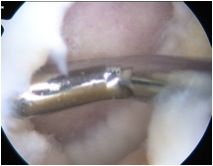

• Cartilage defects

• Background

• Management